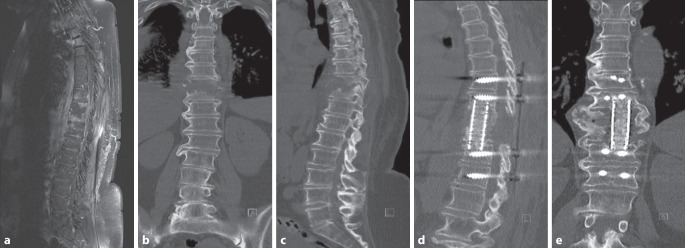

Methods: This retrospective study included 29 patients with pyogenic spondylodiscitis who underwent surgical debridement, interbody fusion, and pedicle screw fixation between February 2018 and March 2023. Patients received PerOssal carriers loaded with either gentamicin (Group A, n = 14) or vancomycin (Group B, n = 15). Clinical outcomes, including fusion rates, infection control, complications, and inflammatory markers, were analyzed.

Results: Baseline characteristics between groups were comparable. Fusion rates at 3-6 months' follow-up were 92.8% (13/14) in Group A and 80.0% (12/15) in Group B, without significant differences (P > 0.05). Both groups showed significant reductions in white blood cell counts and C‑reactive protein levels postoperatively, without inter-group differences (P > 0.05). Complications included cerebrospinal fluid leakage, hematoma, pulmonary embolism, and wound infections, all managed successfully with no recurrent infections observed.

Conclusion: In the short term, PerOssal carriers loaded with either gentamicin or vancomycin demonstrated effective infection control for pyogenic spondylodiscitis and high interbody fusion rates. Moreover, no apparent adverse effects on bone healing were associated with the local administration of high-concentration antibiotics.